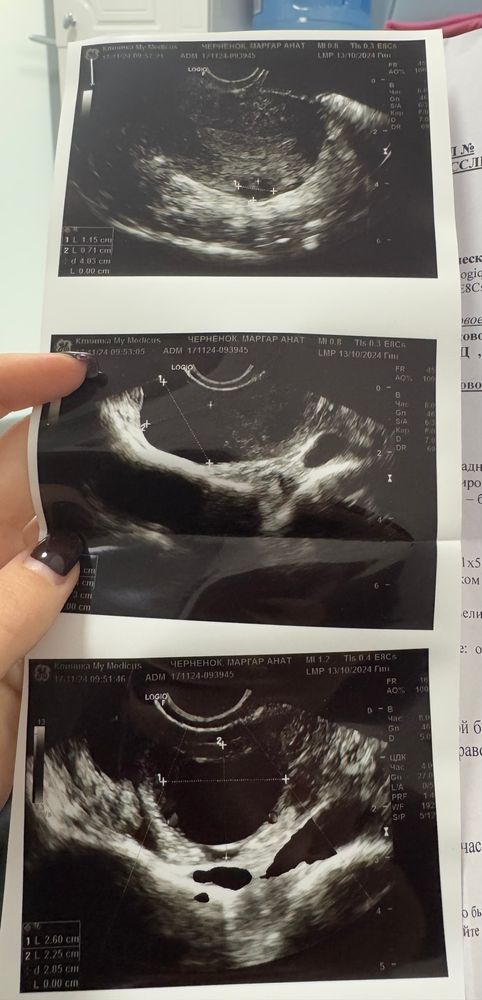

Здравствуйте девочки .Тесты полосятся, хгч сдала только сегодня (результат жду завтра) Сходила сегодня на узи , по узи ничего не увидели , напугали внематочной беременностью так как в матке ничего нет и есть коричневые выделения 😔Сказали пить Транексам.Еще на яичнике в котором было оплодотворение, большая киста функциональная .И подозрение на кровь в позадиматочном пространстве .Переживаю ужасно 😢